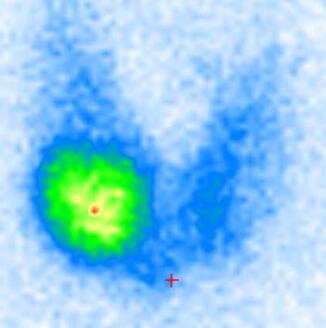

Die Schilddrüsenszintigraphie dient zur bildlichen Darstellung und Funktionsbeurteilung der Schilddrüse. Meist liegt eine knotig umgebaute Schilddrüse, eine Vergrößerung oder eine Funktionsstörung (Über- oder Unterfunktion) vor. Anhand der Szintigraphie können Knoten dann in heiße, kalte oder unauffällige Knoten eingeteilt werden. In der Regel erfolgt zusätzlich eine Untersuchung der Schilddrüse nach Größe und Herdbefunden durch Ultraschall.

Es wird eine leicht radioaktive Substanz (Tc-99m-Pertechnetat) in die Vene gespritzt. Diese Substanz wird ähnlich wie Jod von den Schilddrüsenzellen aufgenommen. Die Strahlenexposition ist sehr gering (ca. 1 mSv) und vergleichbar mit der eines Röntgenbildes. Die verwendete Substanz wird sehr gut vertragen, allergische Reaktionen oder unerwünschte Nebenwirkungen sind nicht bekannt. Nach ca. 15 - 20 Minuten wird eine Aufnahme des Halses und der Injektionsstelle am Arm angefertigt und anschließend werden Bilder mit Hilfe moderner Computersysteme erstellt. Sie erleichtern uns den Ablauf, wenn Sie am Tag der Untersuchung auf Halsschmuck und hochgeschlossene Kleidung (z.B. Rollkragenpullover) verzichten.